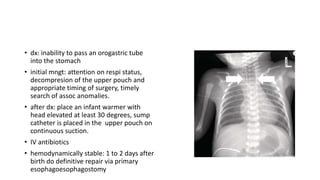

• dx: inability to pass an orogastric tube

into the stomach

• initial mngt: attention on respi status,

decompresion of the upper pouch and

appropriate timing of surgery, timely

search of assoc anomalies.

• after dx: place an infant warmer with

head elevated at least 30 degrees, sump

catheter is placed in the upper pouch on

continuous suction.

• IV antibiotics

• hemodynamically stable: 1 to 2 days after

birth do definitive repair via primary

esophagoesophagostomy